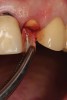

A 65-year-old male patient presented to the office with a fractured maxillary left lateral incisor (Figure 16). Radiographic analysis revealed minimal buccal bone. Having deemed the tooth nonrestorable, the clinician presented several options to the patient, which they carefully reviewed together. A socket-shield approach was selected with the goal of maintaining existing gingival zenith long-term.

Fig 16. Patient presented with fractured maxillary left lateral incisor. Radiographic analysis (not shown) revealed minimal buccal bone. A socket shield was planned during tooth extraction to preserve gingival contours.

Figure 16